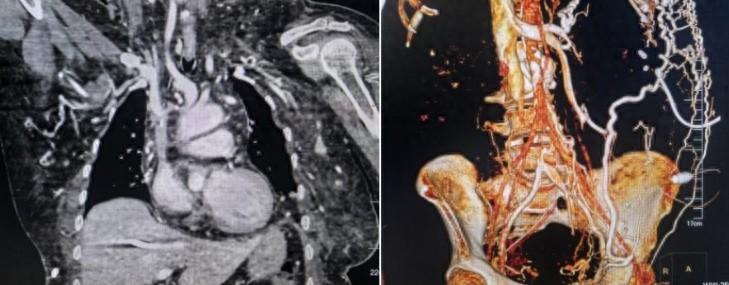

61岁的向奶奶8年前因慢性肾炎恶化导致肾功能衰竭、尿毒症,在经历腹膜透析、内瘘透析失败后,先后行双侧股静脉置管、右侧颈内静脉置管行血液透析,随着长期的置管和透析,患者的深静脉接二连三地闭塞,最终出现右侧颈内静脉-双侧无名静脉-上腔静脉以及双侧股-髂静脉闭塞。患者没有了可用的透析通路,为求进一步治疗,入住中南大学湘雅三医院放射科。

该患者因右侧颈内静脉-双侧无名静脉-上腔静脉以及双侧股-髂静脉闭塞失去了经深静脉长期透析管置管机会,只能另寻其他路径。

放射介入病房梁琪副教授在详细评估患者病情后,考虑可尝试经皮穿刺肝静脉后经肝静脉-下腔静脉-右心房透析管置入,但上述方案非常规手术操作,文献也鲜有记载。与患者及家属反复沟通后,患者家属表示没有透析通路患者也无法存活,即使冒再大的风险也要尝试。

当天晚上,血透通路MDT团队展开多学科讨论,精心设计手术方案与风险预案,先由彩超科刘稳刚副教授行彩超引导下经皮穿刺肝静脉,成功置入导丝,然后由放射介入病房梁琪团队联合肾内科血透室徐勇博士在DSA引导下行经肝静脉-下腔静脉-右心房透析管置入术,手术共历时40min,术中患者生命体征平稳,无任何并发症发生,术后第二天,患者试用透析通路功能良好,顺利出院。